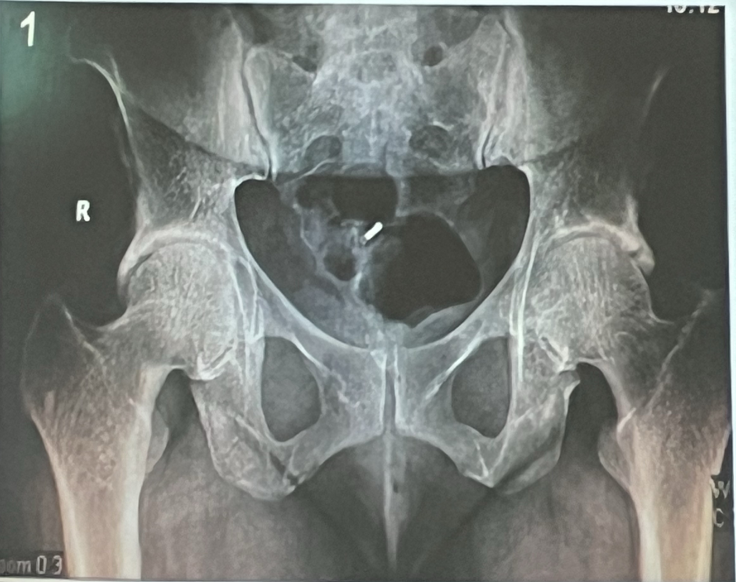

A

Pincer en cabeza derecha